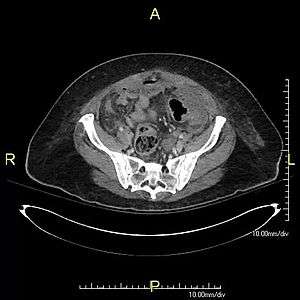

Stercoral perforation

Stercoral perforation is the perforation or rupture of the intestine's walls by its internal contents, such as foreign objects, or, more commonly, by hardened feces (fecalomas) which may form in long constipations or other diseases which cause obstruction of transit, such as Chagas disease, Hirschprung's disease, toxic colitis and megacolon.

Stercoral perforation is a very dangerous, life-threatening situation, as well as a surgical emergency, because the spillage of contaminated intestinal contents into the abdominal cavity leads to peritonitis, a rapid bacteremia (bacterial infection of the blood), with many complications.